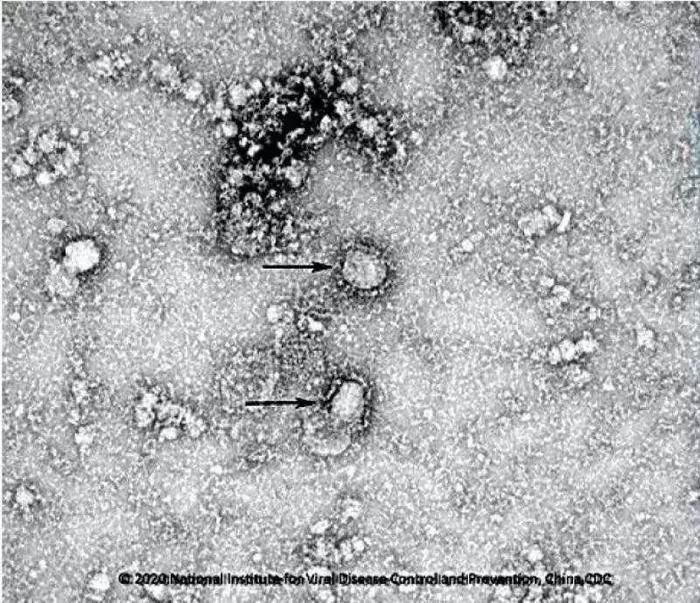

資料圖:新型冠狀病毒武漢株01 圖片來源:中國疾控中心網